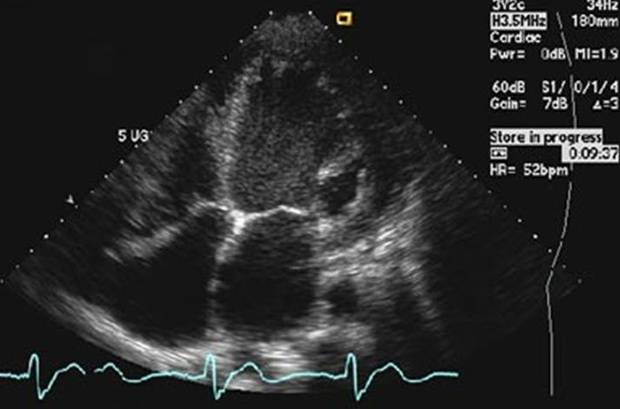

Uma frequência cardíaca muito baixa faz com que menos oxigênio circule pelo corpo. Com você deitado e quieto, ou mesmo dormindo, é provável que não haja nenhum problema se seu coração estiver com apenas 30 bpm. Mas essa frequência com você desperto, em pé, pode provocar desmaios e, em casos extremos, levar à morte

Para um jovem saudável, a frequência normal fica entre 60 e 90 bpm. Mas um atleta, por exemplo, pode ter uma frequência de 40 bpm e isso ser absolutamente normal. É que o coração dele é muito eficiente: cada bombeada entrega ao corpo bem mais sangue que o normal, por isso ele precisa bater menos vezes

O coração tem dois movimentos: a diástole (quando o órgão se enche de sangue) e a sístole (quando o sangue é bombeado para o corpo). Quando o coração acelera, ele encurta a diástole. Assim, o órgão envia menos sangue para o corpo, causando cansaço e desmaios. Uma frequência cardíaca perto dos 180 bpm é sinal de alerta total e perigo de morte